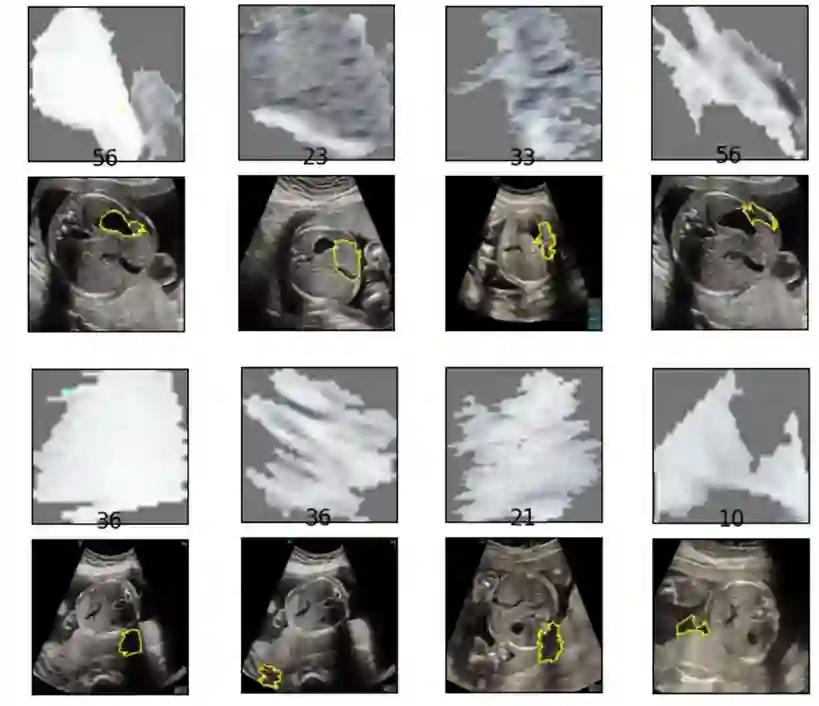

Although deep neural networks (DNN) have achieved state-of-the-art performance in various fields, some unexpected errors are often found in the neural network, which is very dangerous for some tasks requiring high reliability and high security. The non-transparency and unexplainably of Convolutional Neural Networks (CNN) still limit its application in many fields, such as medical care and finance. Despite current studies that have been committed to visualizing the decision process of DNN, most of these methods focus on the low level and do not take into account the prior knowledge of medicine. In this work, we propose an interpretable framework based on key medical concepts, enabling CNN to explain from the perspective of doctors' cognition. We propose an interpretable automatic recognition framework for the ultrasonic standard plane, which uses a concept-based graph convolutional neural network to construct the relationships between key medical concepts, to obtain an interpretation consistent with a doctor's cognition. Extensive experiments have empirically shown that our model can meaningfully explain the decision of the classifier and provide quantitative support.

翻译:尽管深度神经网络(DNN)在不同领域取得了最先进的性能,但在神经网络中经常发现一些出乎意料的错误,这对一些需要高度可靠和高度安全的任务非常危险。进化神经网络(CNN)的不透明和不可解释性仍然限制其在许多领域的应用,如医疗和财务等。尽管目前致力于直观DNN决策过程的研究,但这些方法大多侧重于低水平,没有考虑到以前对医学的了解。在这项工作中,我们提出了一个基于关键医学概念的可解释框架,使CNN能够从医生认知的角度解释。我们提议了一个超声波标准平面可解释的自动识别框架,它使用基于概念的图形神经网络来构建关键医学概念之间的关系,以获得与医生认知一致的解释。广泛的实验从经验上表明,我们的模型可以有意义地解释分类师的决定并提供定量支持。